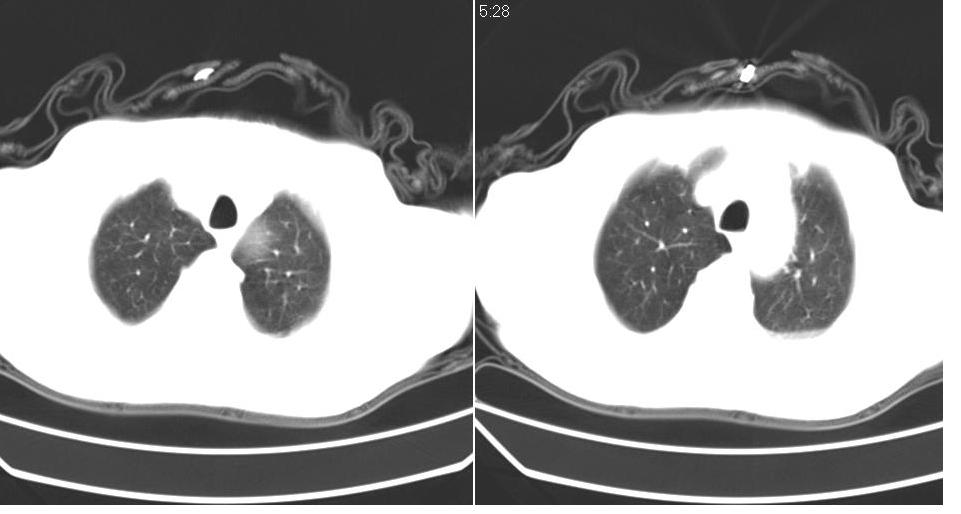

左肺下叶略萎陷、实变,内可见含气支气管征。左舌叶、中叶亦见少许斑片状高密度区,边界不清。纵隔未见肿大淋巴结影。

左下肺体积缩小,密度增高,见片增密影。边界模糊,见支气管充气像,肺门纵隔无异示,心脏气管左移,左侧胸腔少量积液。考虑肺部感染伴部分肺不张[有脑梗塞病史坠积性肺炎可能]

1、左肺下叶后基底段炎症并膨胀不全。

2、左侧胸腔积液。

左肺下叶体积缩小,成类楔形软组织影,其内可见部分含气支气管影,相应左侧肺门区未见明显肿块,考虑炎性病变,建议抗炎后短期复查

3.两肺慢支改变。

左下肺体积缩小,密度增高,并见大片状致密影,边界模糊,其内见支气管充气像,肺门纵隔无异常,心脏气管左移,左侧胸腔少量积液。考虑:左肺炎性病变伴不张。